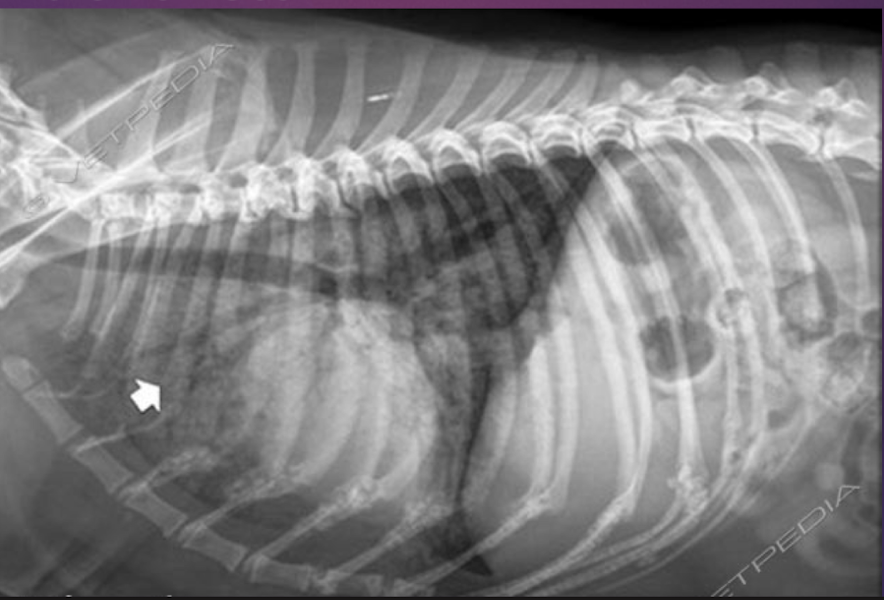

Right or left lateral?

Left